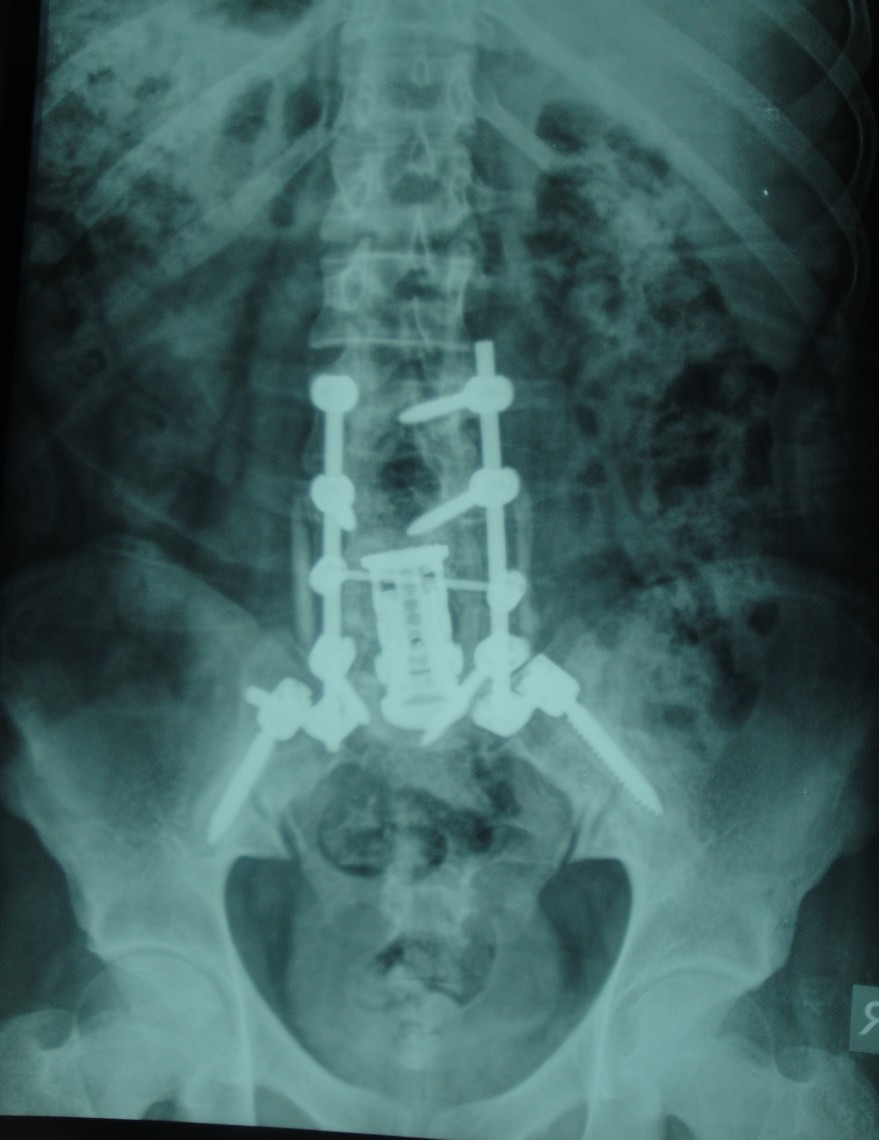

Tümörlere yaklaşım olarak doku tanısı çok önemlidir. O nedenle eğer tümörün odağı bilinmiyorsa ya da omurganın kendi tümörüyse öncelikle biyopsi almak gerekir. Ardından tümörün cinsine göre kemoterapi, radyoterapi, ameliyat ya da bunların kombinasyonu uygulanır.